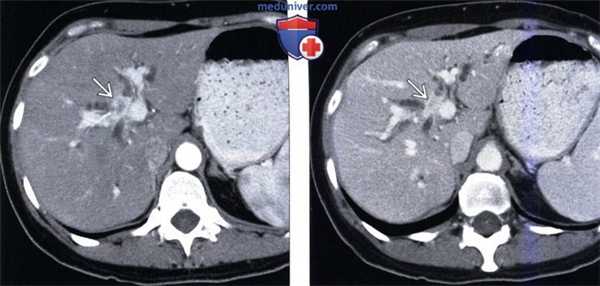

(Слева) На аксиальной КТ с контрастным усилением у девушки 21 года с пальпируемым образованием в эпигастрии в левой доле печени визуализируется опухоль, интенсивно накапливающая контраст. Опухоль имеет несколько неоднородную структуру, в ее центре визуализируется рубец с несколькими небольшими включениями кальция, наличие которых более характерно для фиброламеллярного рака, чем для фиброзной нодулярной гиперплазии.

(Справа) На КТ у этой же пациентки определяется, что образование имеет однородную структуру, вновь визуализируются мелкие кальцинаты в образовании, которое было удалено и верифицировано как фиброламеллярный рак. (Слева) На Т2 ВИ МР томограмме (у мужчины 25 лет с жалобами на раннее насыщение и снижение веса) в печени визуализируется большое образование с гиперинтенсивным сигналом, неоднородной структуры, состоящее из двух долей. Обратите внимание на гипоинтенсивный центральный рубец.

(Справа) На аксиальной Т1 ВИ МР томограмме в артериальной фазе контрастного усиления у этого же пациента визуализируются хорошо отграниченные образования (основное и «сателлитное») неоднородной структуры, с бугристыми контурами, относительно хорошо выраженной васкуляризацией. Фиброзный рубец минимально накапливает контраст в этой фазе, однако в случаях фиброламеллярного рака часто характеризуется персистирующим контрастным усилением в отсроченной фазе.